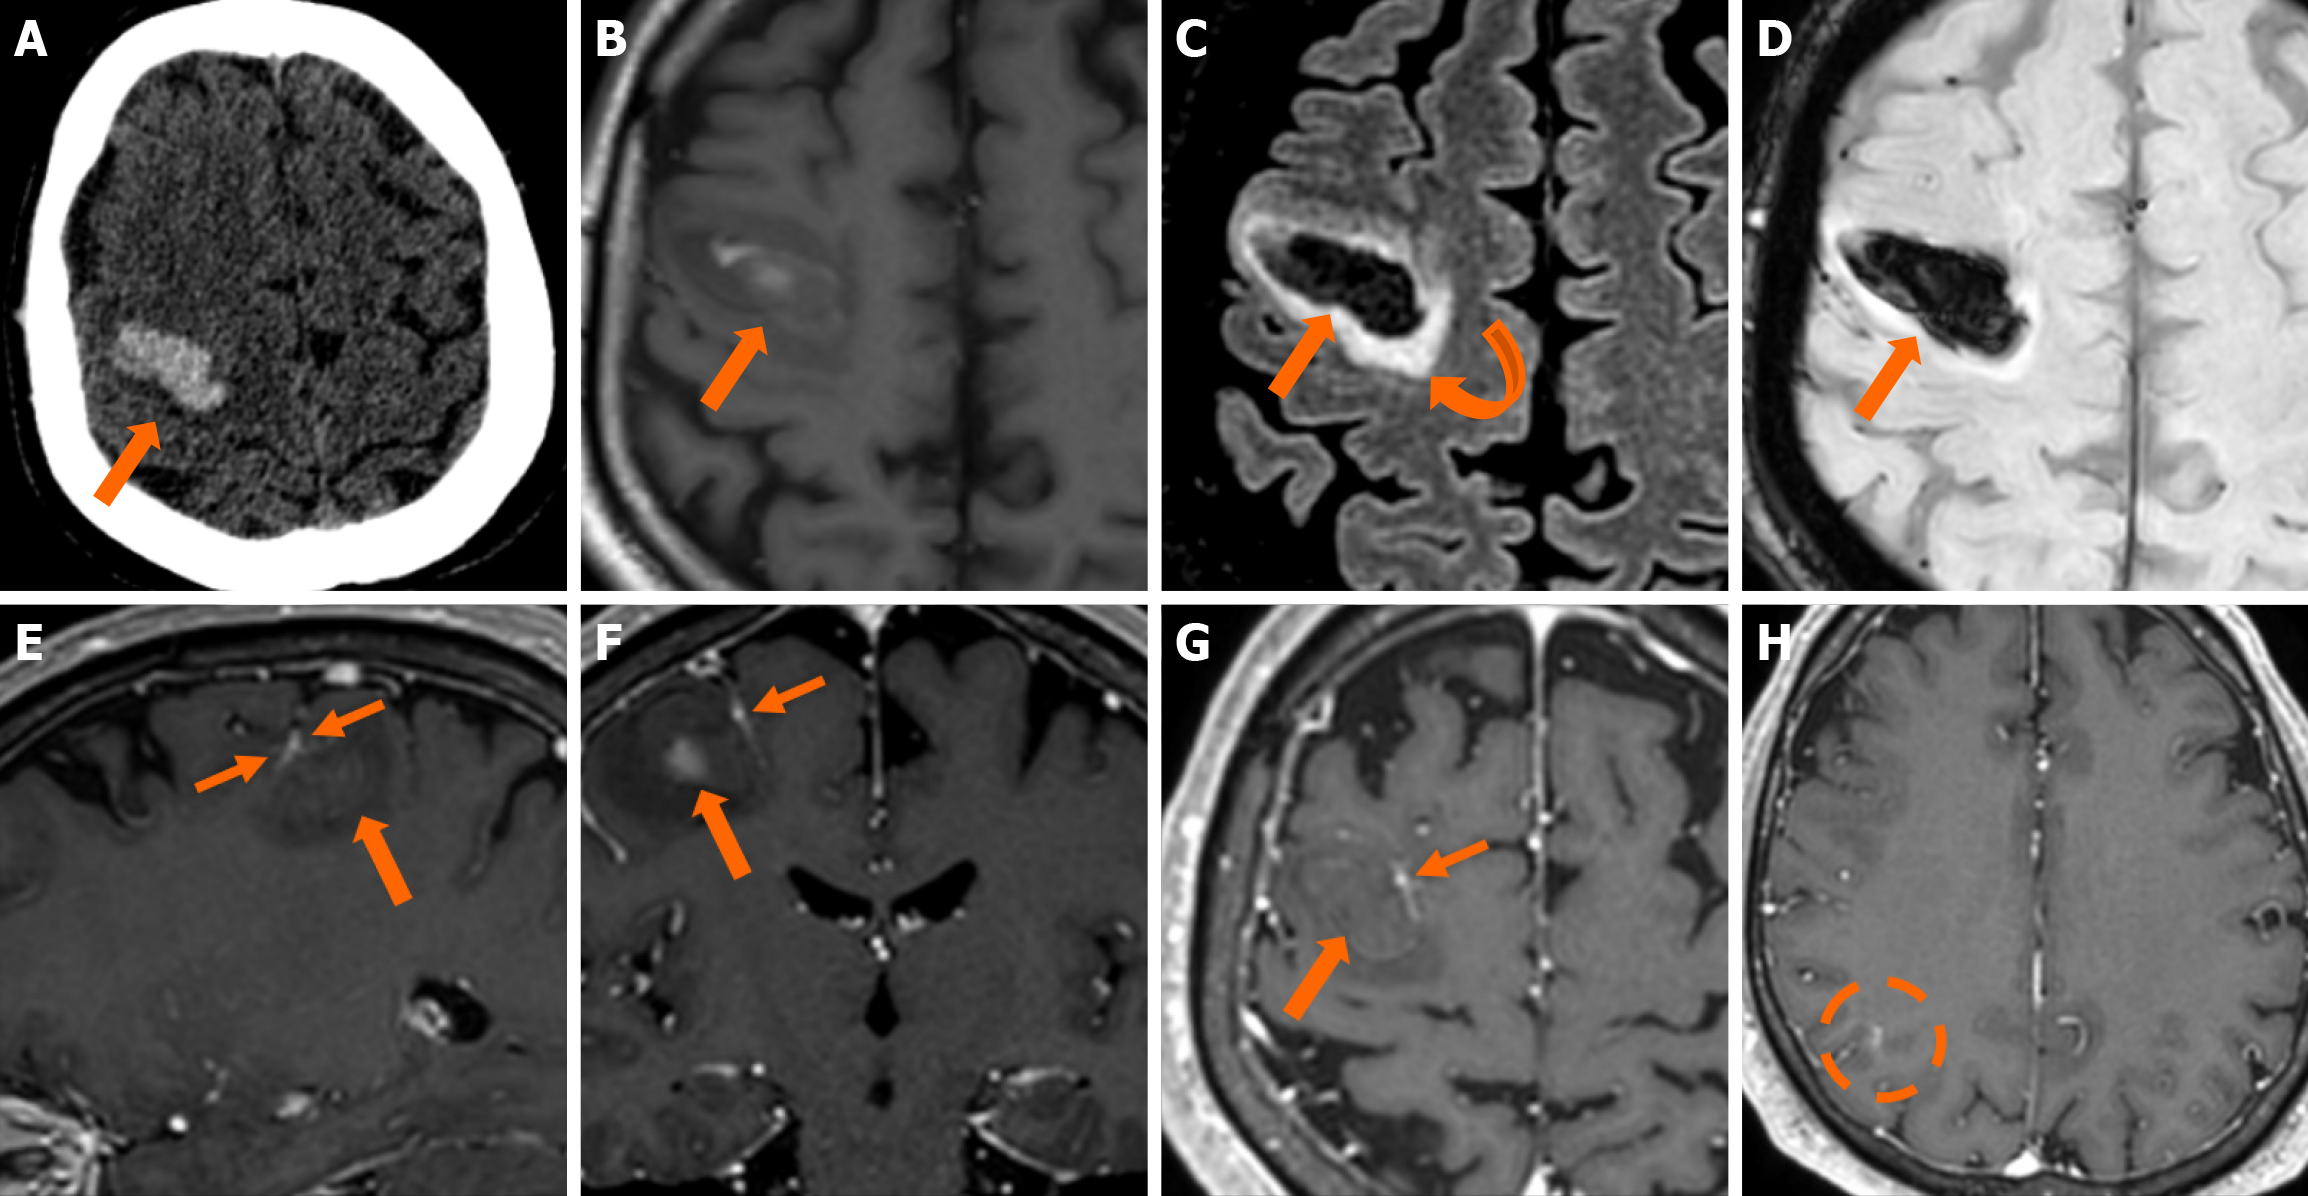

The clinical applicability of the Zabramski classification is still being investigated. A retrospective cohort study evaluating the imaging evolution and clinical trajectory of 255 untreated patients with sporadic CMs over a follow-up period of approximately five years provided evidence that the Zabramski classification may facilitate risk stratification and contribute to treatment planning, particularly in determining the necessity for surgical intervention[89]. Furthermore, a recent study by Saari et al[88] established an association between the radiological characteristics of the Zabramski classification and their clinical relevance, emphasizing that type I lesions have a higher likelihood of becoming symptomatic. Nikoubashman et al[90] suggested an additional category (type V lesions) accounting for cavernomas presenting with gross extralesional hemorrhage. Various examples of CMs on CTs and MRIs, including familial cerebral CM cases, are shown in Figures 4, 5 and 6.

Imaging findings in coexistent DVAs and CMs will be the combination of those described for each malformation separately. Awareness of the possibility of their coexistence may prove invaluable in clinical practice. This is because recognition of a DVA close to a brain hemorrhage may raise suspicion for an underlying CM as the most likely etiology. Additional examinations and follow-up imaging following hematoma resolution will further enhance diagnostic confidence. Figures 8, 9, 10 and 11 illustrate clinical examples in which identifying the synchronous presence of a DVA adjacent to a brain hemorrhage (or suspected brain hemorrhage) enabled the diagnosis of a probable underlying CM as the most likely etiology, thereby avoiding unnecessary examinations or interventions.